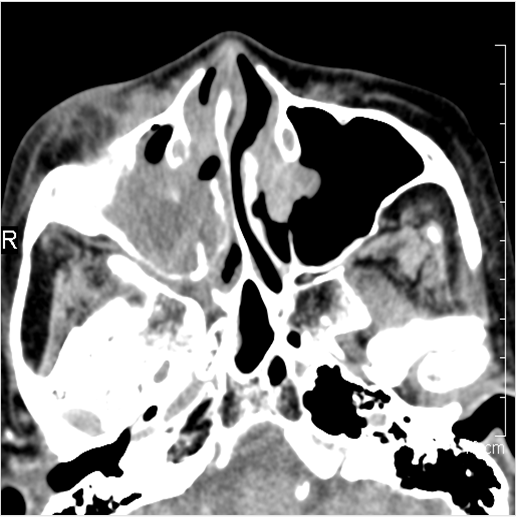

There is infiltration in the posterior nasal cavity or sphenoethmoidal recess that is near to or protruding into the sphenopalatine foramen and pterygopalatine fossa.

There is evidence of bone erosion along the face of the sphenoid bone or pterygoid base or processes.

There is mucoperiosteal thickening in the sinuses.